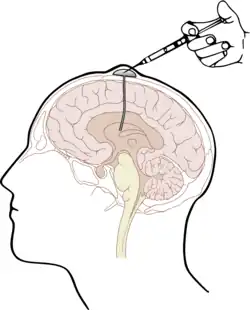

For insertion in mice, a permanent ICV guide cannula must be inserted 1 mm above the lateral ventricle. A trained surgeon is ideal for insertion, and a stereotaxic frame and bone cement are needed. The cannula is implanted through the hindlimb area of the cerebral cortex. The surgeon must be careful to minimize damage to the surrounding brain tissue during this process.[7]

A catheter connected to a subcutaneous reservoir is implanted for permanent access in humans. The reservoir used is most commonly the Ommaya reservoir. A 25-gauge needle is used to puncture the scalp into the reservoir. A few milliliters of CSF are withdrawn before injecting the drug. This technique is typically used for long-term drug administration. Rarely will repeated taps be conducted to administer drugs due to the risk of damaging brain tissue.[13]